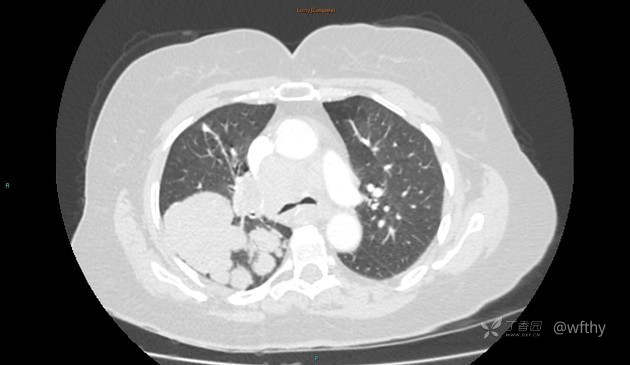

病例女65,头部肿块